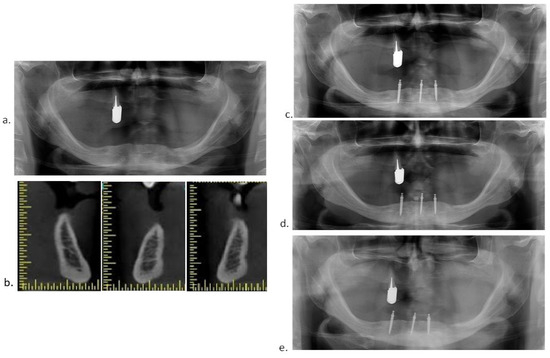

2.4. Surgical Procedures

2.5. Prosthodontic Protocol

2.6. Radiographic Evaluation

3.1. Marginal Bone Level (MBL) Change